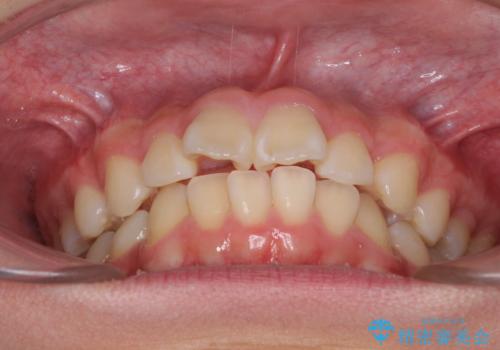

- 上下前歯のデコボコを改善したいとのことで来院された患者様です。

自己管理を減らしたいとのことで、ワイヤー装置による矯正治療を行うこととしました。